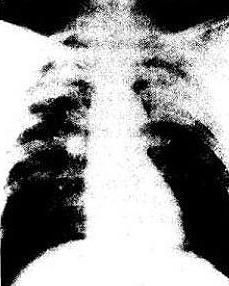

2.X線表現

接觸石英粉塵,特別是吸入高濃度石英粉塵所致典型矽肺的X線表現是首先在兩上肺野出現圓形小陰影。兩側基本對稱,以外側更為明顯。但肺尖不受累及,如肺尖出現陰影則並發肺結核的可能性較大。

隨病情的發展,除兩上肺野外,中、下肺野也出現圓形小陰影,肺內小陰影增多、變大,密集度增高。嚴重的病例,兩肺密集陰影,恰似漫天風雪(暴雪狀)。隨小陰影的增多,肺紋理髮生變形、中斷,直至不能辨認。

大陰影經過幾年的演變,有向肺門和縱隔移動的趨勢,並有肺門上抬,肺下部氣腫加重,殘留的肺紋拉直呈垂柳樣。在肺的周邊部可見疤性肺氣腫,其間有殘留的肺段間隔線。

在接觸高濃度的石英粉塵、病情嚴重的病例,可因矽結節中心壞死後發生矽結節鈣化,並常伴有肺門淋巴結蛋殼樣鈣化。在出現矽結節鈣化後,病情常變緩和,可多年處於穩定狀態。